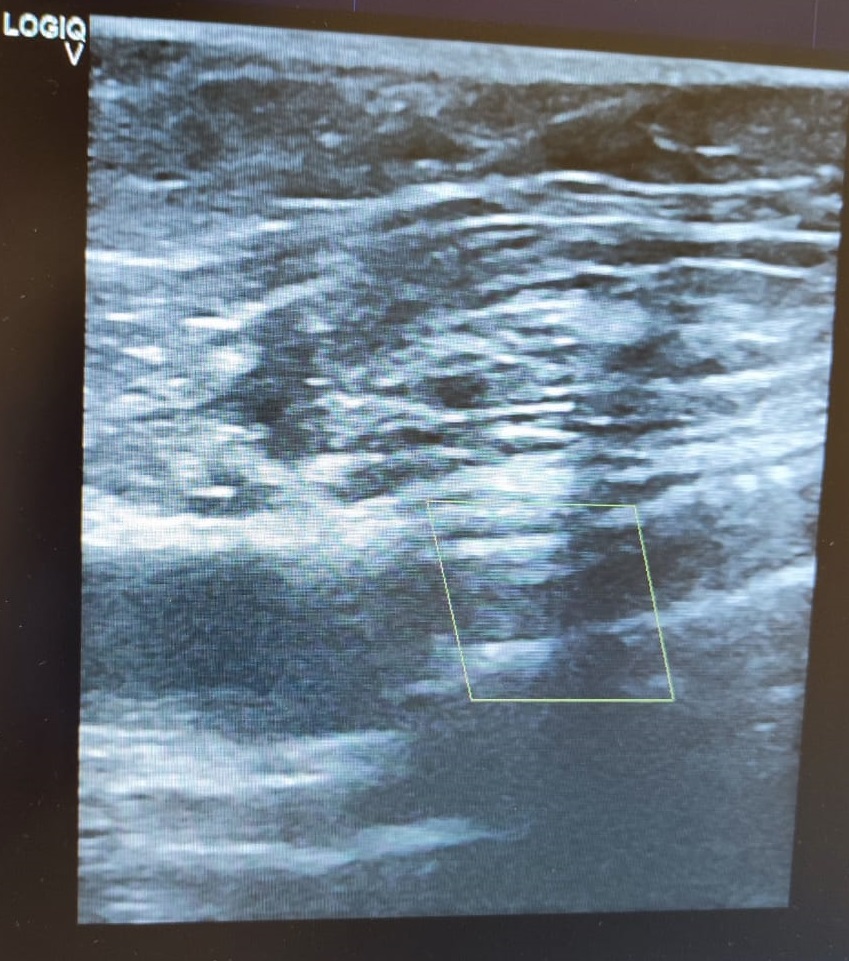

El paciente relata dolor gemelar y aumento de claudicación intermitente. Se realiza ecografía a pie de cama donde se observa trombosis del stent de toda la femoral superficial.

Durante la ecografía se observa sten de la femoral superficial ocluido, observándose flujo en la zona previa al stent y sin observarse flujo sanguíneo en el stent.